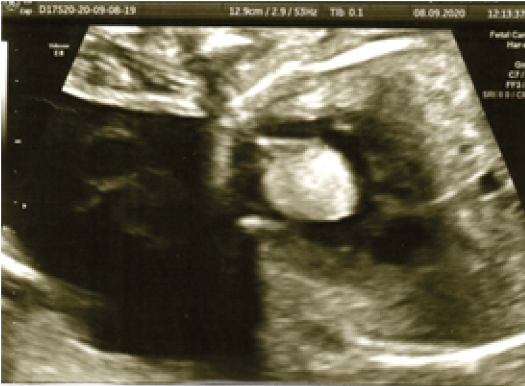

Los rabdomiomas son tumores cardiacos fetales raros que pueden estar presentes hasta un 86 %. Se encuentran mayormente en el tabique interventricular, pared libre de aurícula o ventrículo y poco frecuente en las válvulas auriculoventriculares. Depende del tamaño del tumor para tener repercusión hemodinámica fetal.

Al examen ecográfico se observa lesión hiperecogénica en el tabique interventricular con protrusión a la cavidad ventricular derecha, acompañado de desviación leve del tabique interventricular y asociado al momento del examen con arritmia de tipo ventricular.